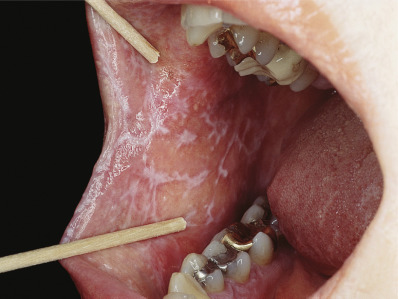

Oral mucosal LP is the most common form of mucosal LP, and it is usually chronic. Between 10% and 15% of patients with oral LP will also have skin lesions. Women represent 50%–75% of patients with oral LP. Oral LP in women begins 10 years later than in men (age 57 vs. 47). Oral lesions may be reticulate (reticular), the oral version of Wickham striae ( Fig. 12.8 ), erythematous (atrophic), or ulcerative (erosive) ( Fig. 12.9 ); lesions are often bilateral and symmetric. The most common pattern in oral LP is the ulcerative form (40% of patients). Usually, reticulate and erythematous lesions are found adjacent to the ulcerative areas. The erythematous pattern is the predominant pattern in 37% of patients, but almost always, reticulate lesions are also seen in these patients. In oral LP, the “classic” reticulate lesions are most prominent in 23% of patients. Rarely patients may have a white plaque mimicking leukoplakia, bullous, or papular lesions. Symptoms are least common in patients with reticulate lesions; 23% are symptomatic, and then only when the tongue is involved. All patients with erosive lesions are symptomatic, usually with burning or pain. Patients may simultaneously have several patterns, so patients are characterized by the primary form they exhibit. Lesions appear on any portion of the mouth, and multisite involvement is common. The buccal mucosa is involved in 90%, the gingiva in more than 50%, and the tongue in about 40%.

On the gingiva, LP may produce desquamative gingivitis (see Fig. 12.9 ). Gingival involvement is particularly difficult to diagnose and often requires biopsy for both histology and DIF to confirm the diagnosis and exclude other autoimmune causes of desquamative gingivitis. Gingival involvement is associated with accelerated gingival recession. Mechanical injury from dental procedures and poorly fitting appliances may trigger or exacerbate gingival LP. On the tongue and palate, lesions are often mistaken for leukoplakia. The lower lip is involved in 15% of oral LP patients, but the upper lip in only 2%. Lower lip LP is frequently mistaken for actinic cheilitis. Imiquimod treatment can lead to exacerbation of the labial LP, with extensive erosion and crusting. Oral LP is stable but chronic, with fewer than 3% of patients having a spontaneous remission in an average 5-year follow-up. Periodontitis appears to exacerbate oral LP, especially gingival disease. Plaque control either by the patient after training or by a dental professional improves the clinical appearance and pain.